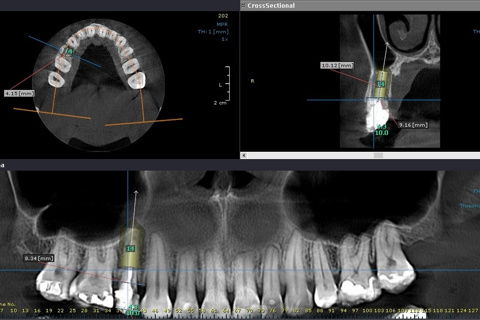

Planejmanento em tomografia

Paciente sexo feminino,aproximadamente 40 anos, encaminhada pelo protesista para exodontia do elemento 14 e implantação. O mesmo verificou trinca na raíz do elemento 14. Após documentação e paciente avaliado o tratamento de opção em comum acordo com a paciente foi , exodontia, implante imediato com ROG (alobone) e enxerto gengival livre para ocluir o alvéolo, com provisório tipo aleta e função tardia. (Caso em andamento).